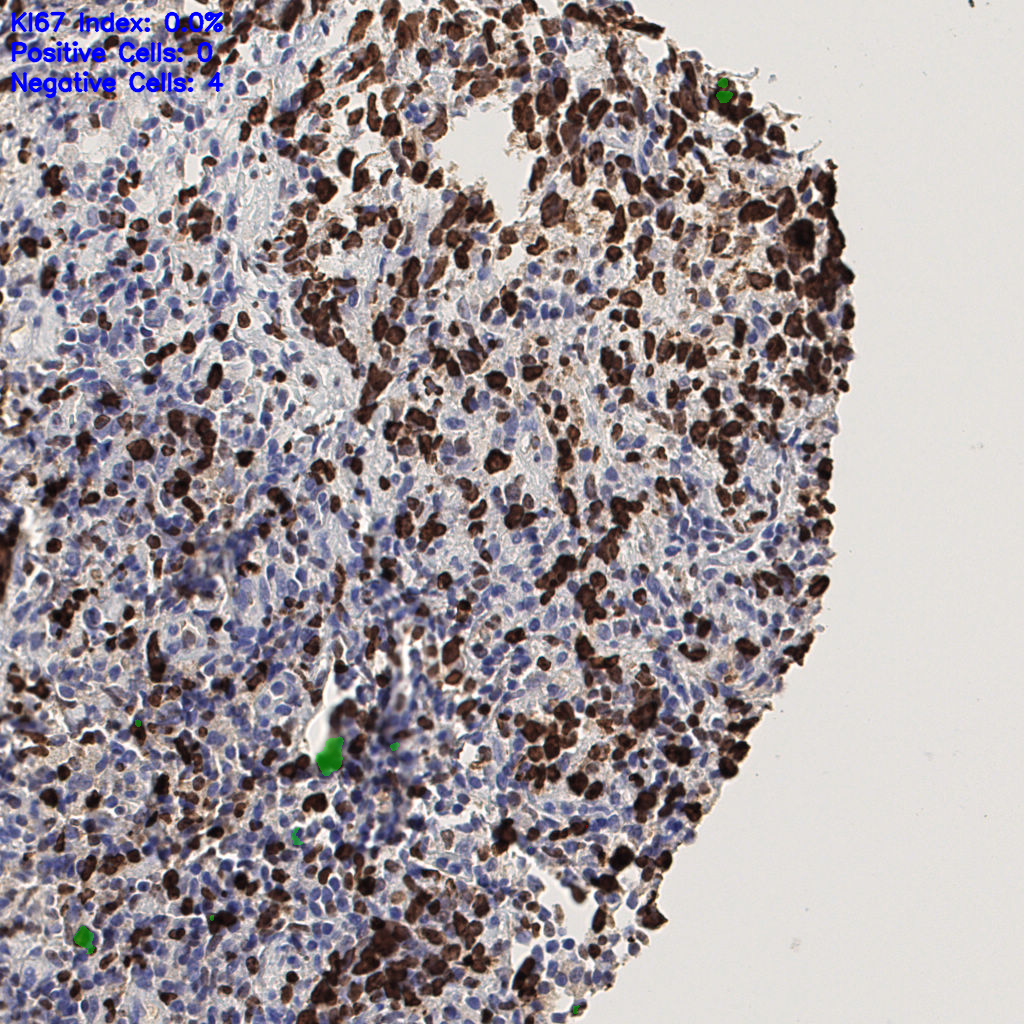

7.85%

Ki67 指数

阴 1104

阳 94

切片统计

总切片

1953

有效

288

已标记

有效率

15%

标记后

标记前